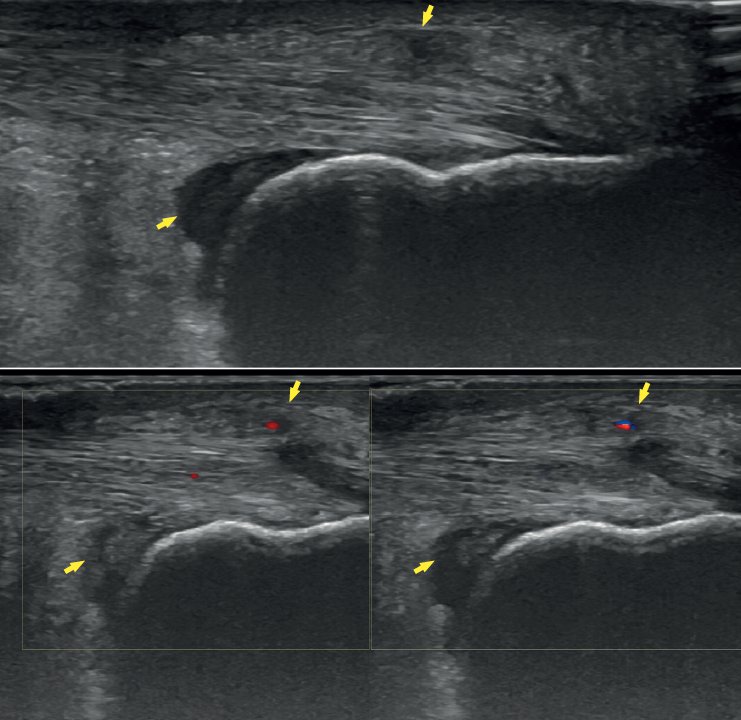

Figure 3. Plain radiography, Sagittal view with weight-bearing. Moderate calcifications in the insertion of the Achilles tendon with intratendinous enthesophyte. Morphological alterations of the posterior tuberosity of the calcaneus.

Plain radiography under loading conditions is the essential initial diagnostic tool(20). It allows us to assess alignments and dysmetria, to measure angles, to determine the morphology of the calcaneus and its posterior tuberosity, to characterise bone exostosis and increments in thickness of the retrocalcaneal soft tissues, and to plan surgical procedures (Figure 3).